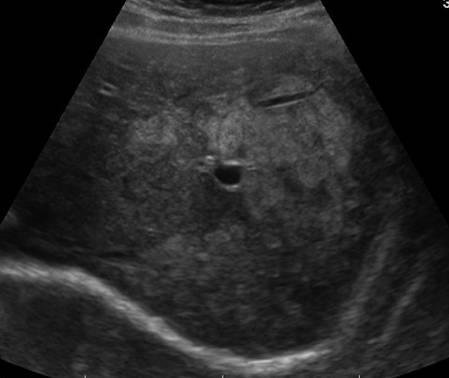

Gan nhiễm mỡ

Gan nhiễm mỡ - Ảnh 2

» Thông tin: Nữ giới – 40 tuổi.

» Lâm sàng: Kiểm tra sức khỏe.